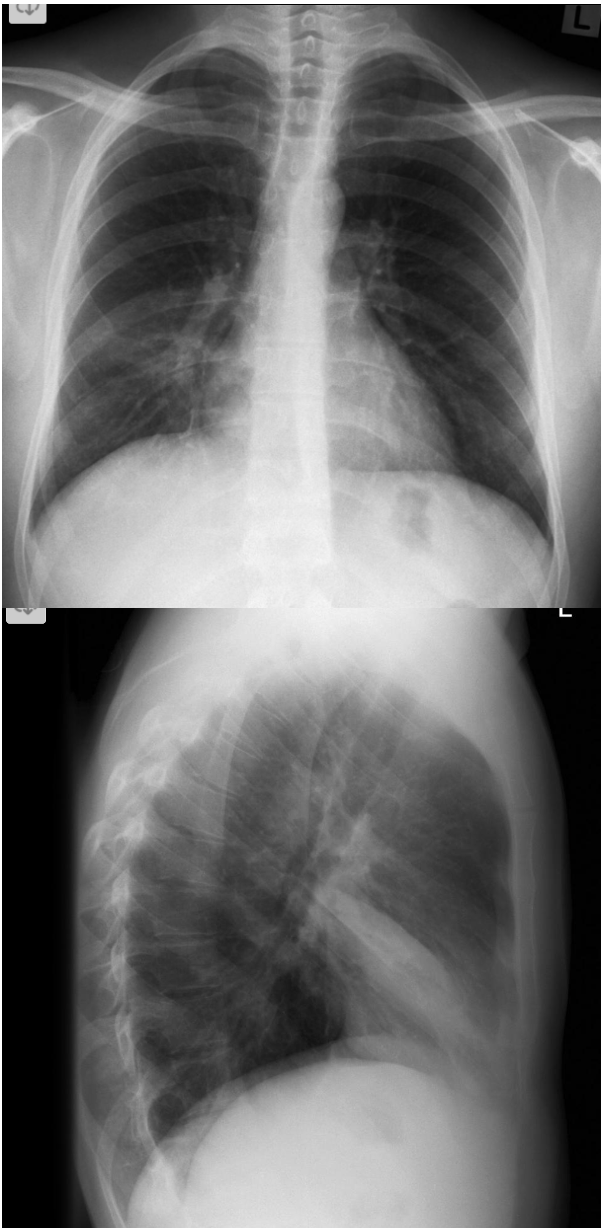

What are the features of RLL collapse on CXR?

A

CXR features: (7)

Triangular opacity in RLZ medially with apex pointing toward R hilum

Obscured medial R hemidiaphragm

Inferior displacement of the right hilum

Obscured descending interlobular pulmonary artery

Distinct R heart border

Inferior displacement of horizontal fissure

Elevation of R hemidiaphragm

Crowding of R sided ribs

Shift of mediastinum to the right

Lateral CXR:

Triangular opacity in lower posterior chest

Obscured post R hemidiaphragm

Increased attenuation over the lower thoracic vertebrae

Oblique fissure displaced posteroinferiorly

Inferior displacement of R hilum